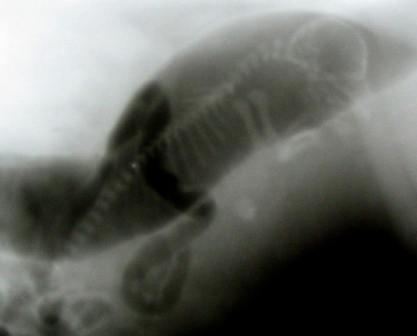

Röntgenaufnahme wenige Minuten vor der Geburt... und einige Stunden später